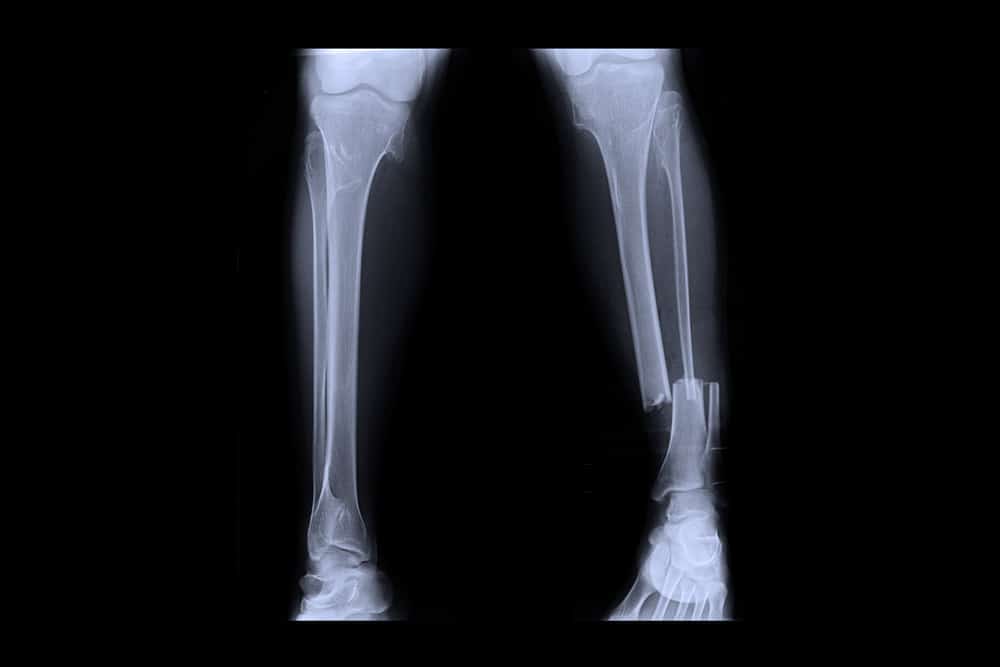

ब्रोकन लोअर लेग नाम से ही स्पष्ट हो रहा है कि यह पैर के निचले हिस्से की हड्डी को टूटने को कहा जाता है। जिस कारण से व्यक्ति चल नहीं पाता है। कुछ मामलों में पैर के निचले हिस्से में पाई जाने वाली हड्डी टीबीया (Tibia) और फिबुला (Fibula) बोन टूटने के कारण त्वचा से बाहर की ओर निकलने लगती है।

लोअर लेग का हिस्सा दो हड्डियों से मिल कर बना होता है, जिसे टीबीया और फिबुला कहते हैं। अक्सर फिबुला की तुलना में टीबीया फ्रैक्चर ज्यादा होता है। जिसके लिए लोअर लेग के फ्रैक्चर को टीबीया फ्रैक्चर (Broken (fracture) lower leg) भी कहते हैं। इसी तरह जब फिबुला फ्रैक्चर हो जाता है तो उसे फिबुला फ्रैक्चर कहते हैं। इस कंडीशन को ही ब्रोकन लोअर लेग भी कहते हैं।

- एक्स-रे (X-rays)- एक्स-रे से ब्रोकन लोअर लेग की स्थिति को समझा जाता है। इसे ठीक होने में एक सप्ताह या एक महीने तक का वक्त लग सकता है।